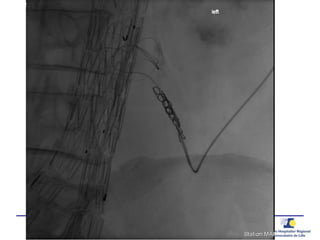

Guide de pression 0.014’’

20 G needle0.014’’ PressureWire

 Pression

Aorta

Sac